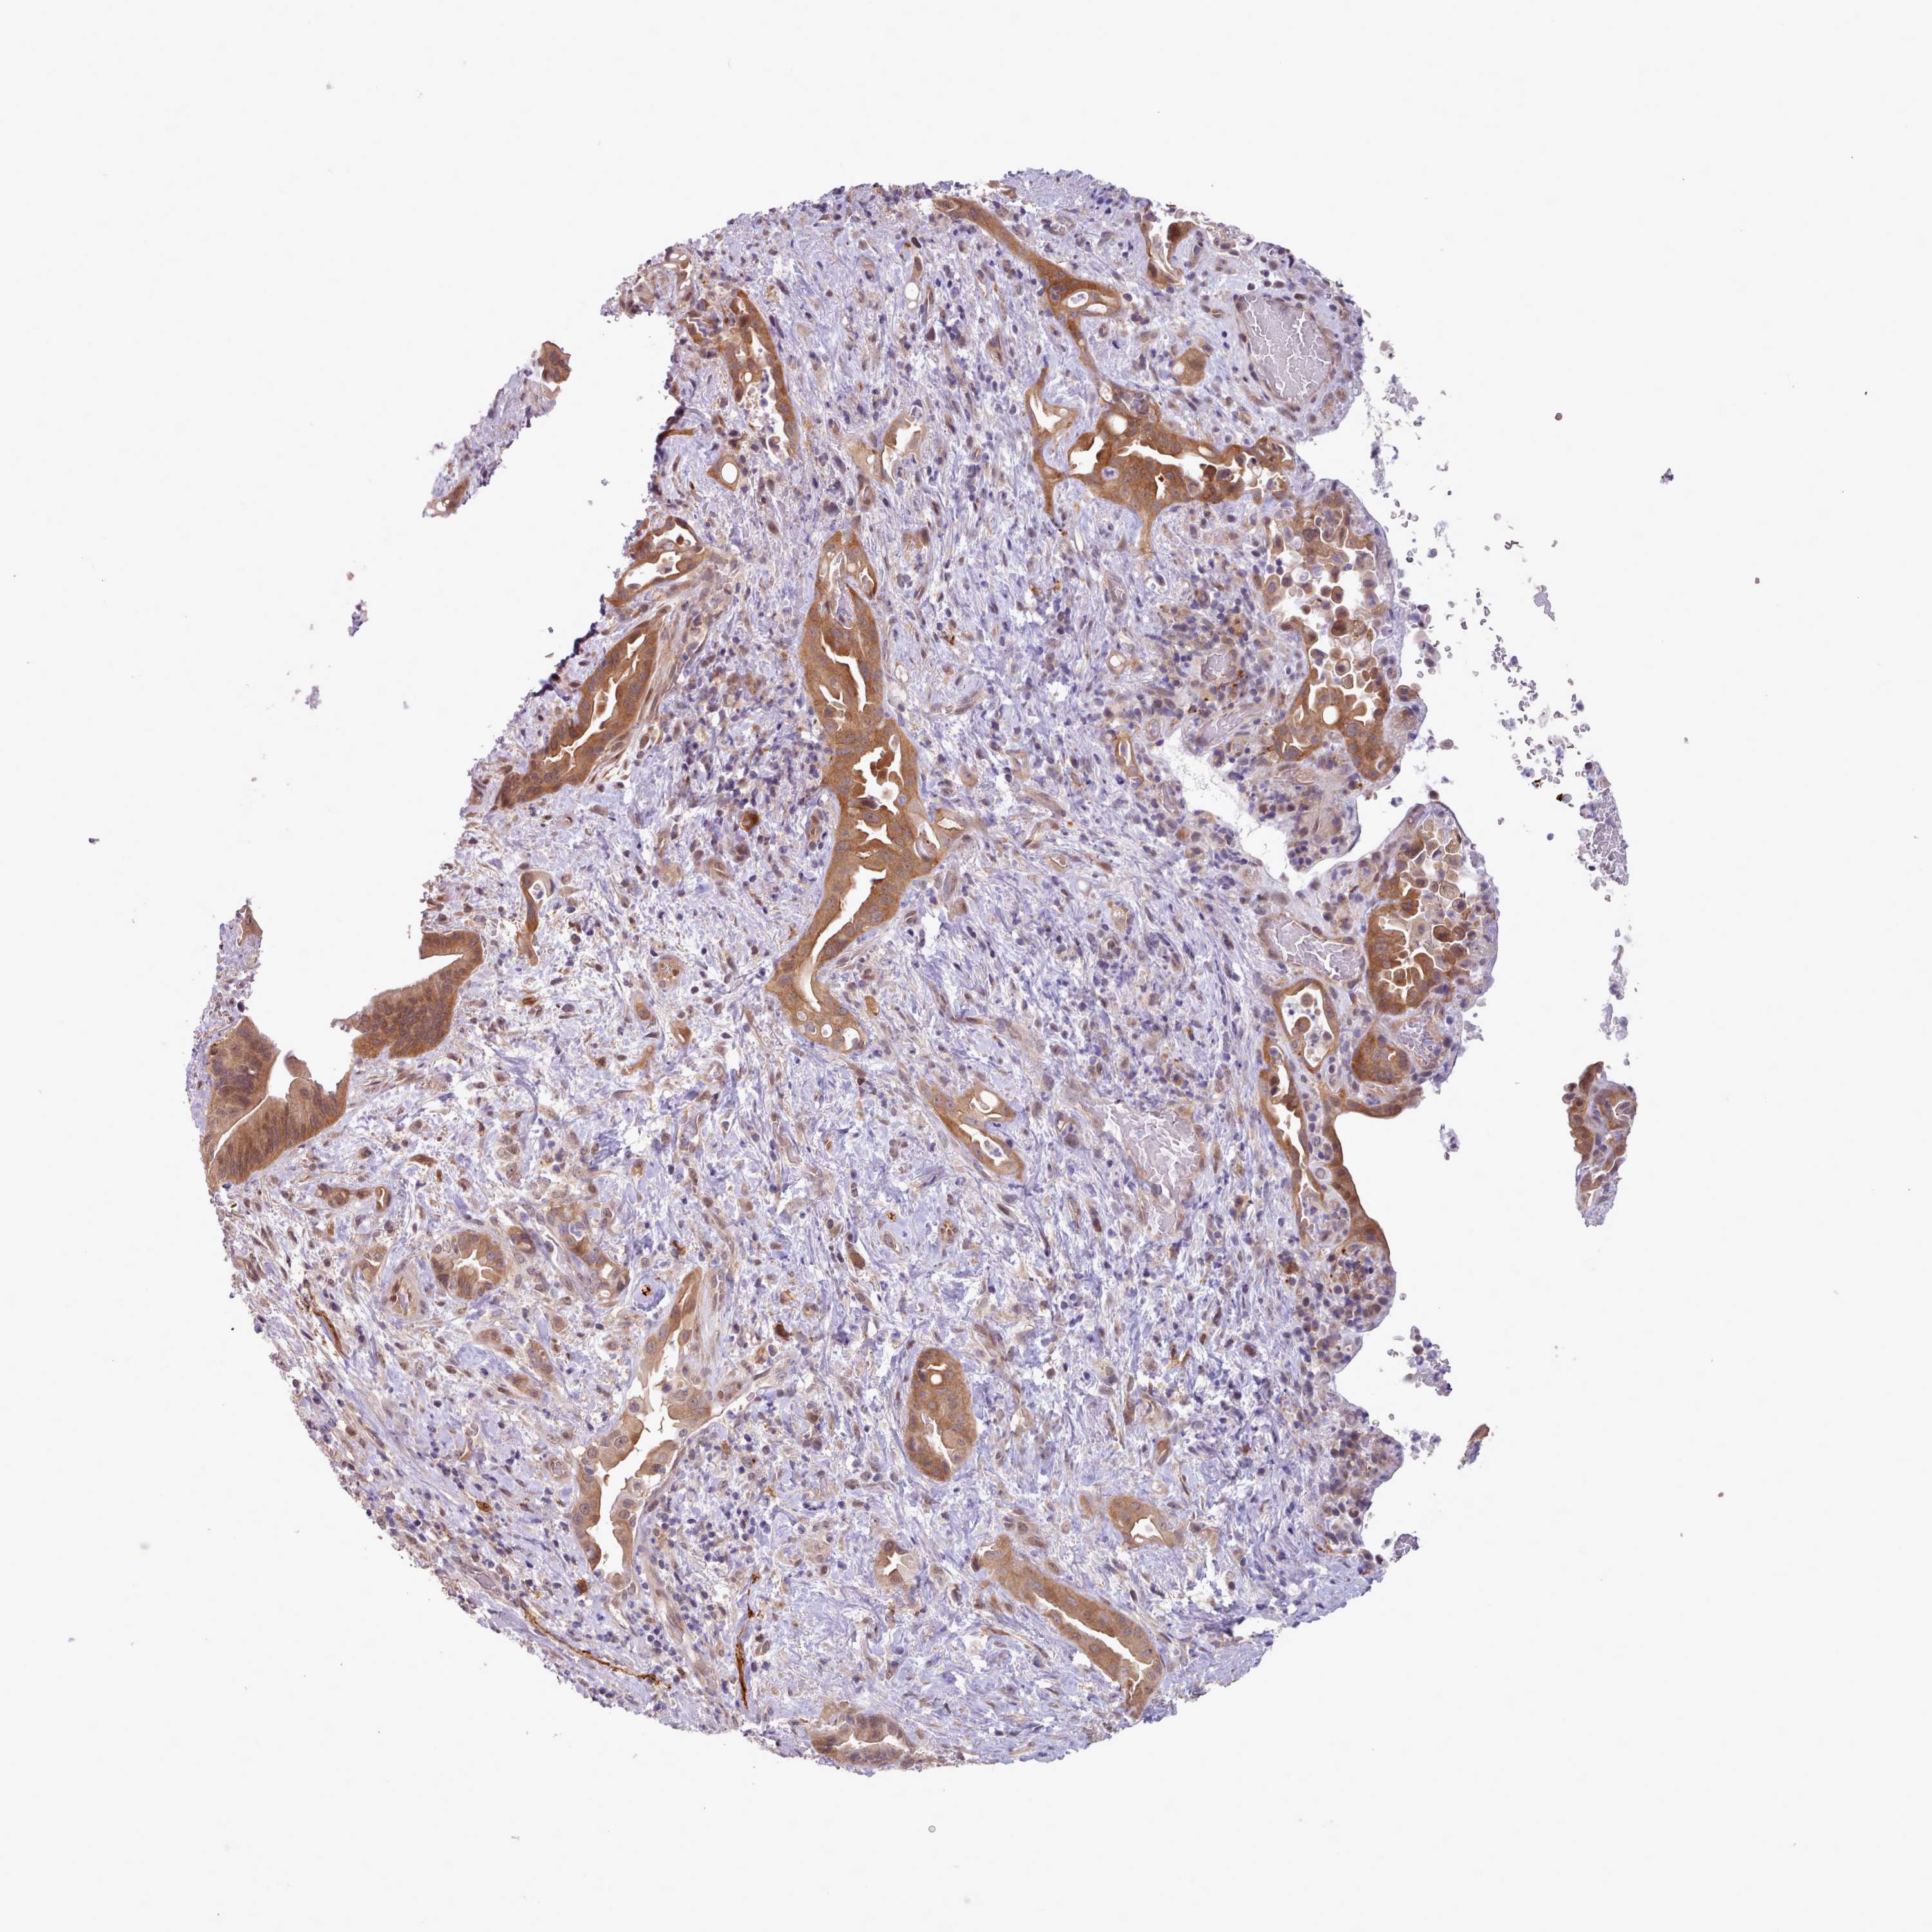

LIVER CANCER - Protein expressioni

A mouse-over function shows sample information and annotation data. Click on an image to view it in a full screen mode. Samples can be filtered based on level of antibody staining by selecting one or several of the following categories: high, medium, low and not detected. The assay and annotation is described here.

Note that samples used for immunohistochemistry by the Human Protein Atlas do not correspond to samples in the TCGA dataset.

Antibody stainingi

Antibody staining in the annotated cell types in the current human tissue is reported as not detected, low, medium, or high, based on conventional immunohistochemistry profiling in selected tissues. This score is based on the combination of the staining intensity and fraction of stained cells.

Each image is clickable and will lead to virtual microscopy that enables deeper exploration of all samples and also displays staining intensity scores, fraction scores and subcellular localization as well as patient and tissue information for each sample.

Antibody HPA041008

Antibody HPA041307

Staining

High

Medium

Low

Not detected

Intensity

Strong

Moderate

Weak

Negative

Quantity

>75%

75%-25%

<25%

None

Location

Nuclear

Cytoplasmic/membranous

Cytoplasmic/membranous,nuclear

Cholangiocarcinoma

Carcinoma, Hepatocellular, NOS